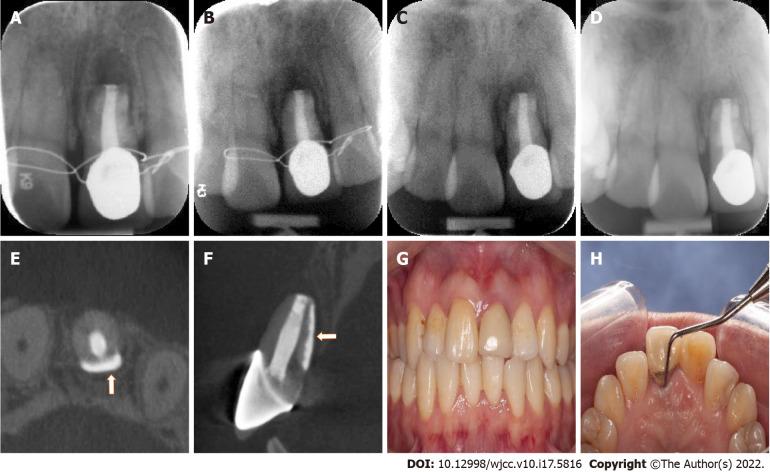

This case report describes a woman who had a sinus tract on the labial gingiva of the left maxillary central incisor for past two months. Periodontal probing revealed an 8-10 mm deep, narrow, isolated pocket on the palatal side of the tooth. Clinical and radiographic examination confirmed a longitudinal root fracture. A new approach using a combination of resin and iRoot BP Plus through intentional replantation was used for the treatment of the tooth. At one-year follow-up, the tooth remained asymptomatic with normal periodontal probing depth, and radiographic images showed almost normal bone and periodontal structures around the root.

本病例报告描述了一名女性,其左上颌中切牙唇侧牙龈有窦道已持续两个月。牙周探诊显示该牙腭侧有一个8-10毫米深、狭窄且孤立的牙周袋。临床和影像学检查证实为纵向根折。采用树脂和iRoot BP Plus联合通过有意再植的新方法对该牙进行治疗。随访一年时,该牙无症状,牙周探诊深度正常,影像学图像显示牙根周围的骨和牙周结构几乎正常。